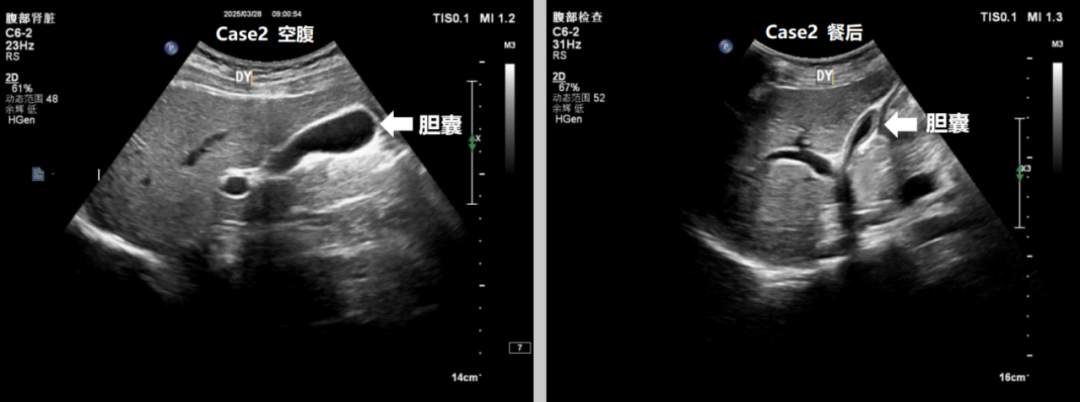

二、机体在进食时胆囊受到胃肠道的刺激后会收缩,并将胆汁释放到小肠中参与消化,这时胆囊就会缩小(如图餐后胆囊),像漏了气的皮球,胆囊腔内及胆囊壁上的一些小的病灶(如腔内小结石,壁上小息肉)就很难显示出来,所以为了更好的显示胆囊,必须空腹检查。

空腹就是彩超检查前一天清淡饮食,不要吃容易产生气体的食物(比如豆制品、牛奶、肉类等),晚上8点后就不要再吃东西了,晚上10点以后不要再喝水。被检查者一般需空腹8~10小时,以保证胆囊、胆管内胆汁充盈(如图空腹胆囊),并减少胃肠道食物和气体的干扰。因此空腹超声检查选择在上午检查效果最好。